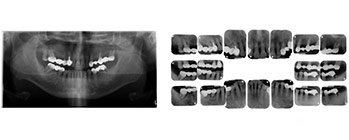

7、全口10枚或18枚根尖片,環口X光等搜集

綜合診斷與治療分析(圖03-07)